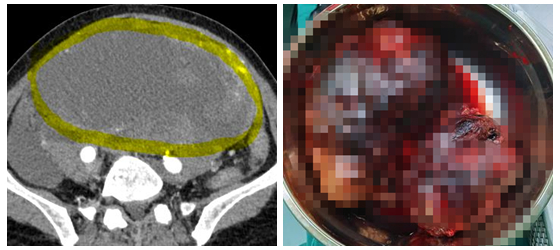

入院后,普外科医疗团队为患者进行了增强CT等全面检查。影像学显示:肿瘤体积巨大、血供丰富,由肠系膜下动脉供血且无法栓塞,与直肠、小肠、输尿管等重要脏器关系密切,手术难度和风险极高。面对这一复杂病例,医院迅速组织普外科、影像科、麻醉科、手术室等多学科专家进行会诊,对肿瘤位置、毗邻关系、血供特点进行精准评估,制定了周密的手术方案和应急预案。

3月3日,廖国庆教授带领团队为患者实施腹腔巨大肿物切除手术。术中探查发现,肿瘤与周围组织粘连严重、位置深、分离难度大。廖教授团队凭借丰富的临床经验和精细的手术操作,术中发现肿瘤来源于直肠,由于直肠位于盆腔内,手术操作空间小,加上肿瘤巨大,明显增加了手术难度,仔细分离肿瘤与周围脏器的粘连,通过精细操作完整切除肿瘤,并有效控制术中出血,成功保护了直肠、小肠、输尿管等重要器官。